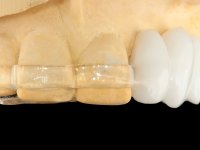

O estudo imagiológico para a colocação dos implantes, começou com a realização em laboratório de uma guia com dentes em sulfato de bário. Esta guia foi colocada em boca conjuntamente com marcas de referência coladas aos dentes, também em sulfato de bário. A guia foi estabilizada com cera mole. A TAC foi realizada com estas referências colocadas em boca. Após a realização da TAC foi feita uma impressão de arrasto em silicone. Esta impressão foi vazada a gesso em laboratório e posteriormente digitalizada. A digitalização do modelo com as referências foi sobreposta á imagem da TAC, permitindo uma planificação apurada na colocação dos implantes. Na planificação foi decidido colocar 2 implantes no local dos dentes 2.3 e 2.4 evitando-se a zona do 2.2 com pouco osso e o seio maxilar. Este estudo deu origem a uma guia cirúrgica que orientou a colocação dos implantes. Durante o período de osteo-integração a paciente utilizou a prótese removível rebasada com acondicionador de tecidos. A guia cirúrgica mostrou-se também útil na exposição dos implantes mostrando a sua localização precisa e orientando a incisão. A impressão definitiva foi realizada utilizando a técnica de moldeira aberta após eliminação do attachment. No laboratório foi confeccionada uma ponte metalo-cerâmica de 3 elementos com o elemento 2.2 em suspensão. A ponte após verificação e aprovação foi cimentada. A reabilitação apesar de pouco extensa (sem o elemento 2.6) mostrou-se capaz estetica e funcionalmente.